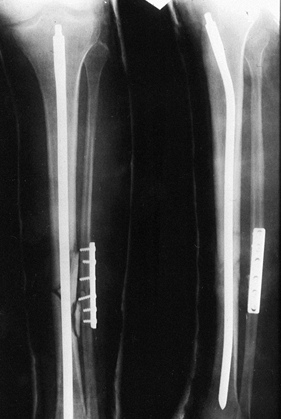

Figure 24.5. Radiographic examples of the four grades of tibial fracture severity. A: Minor severity: spiral fracture caused by a simple slip and fall. B: Moderate severity: transverse fracture in a pedestrian struck by slowly moving vehicle. C: Major severity: comminuted fracture with tibial-fibular diastasis caused by a high-velocity motorcycle crash. D: Major severity: near amputation caused by a high-speed motorcycle accident; with segmental bone loss.